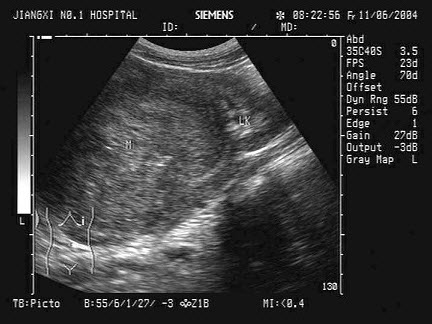

5、单项选择题

如图,初步超声诊断为()

A.二尖瓣返流

B.三尖瓣返流

C.主动脉瓣返流

D.肺动脉瓣返流

E.以上均不是